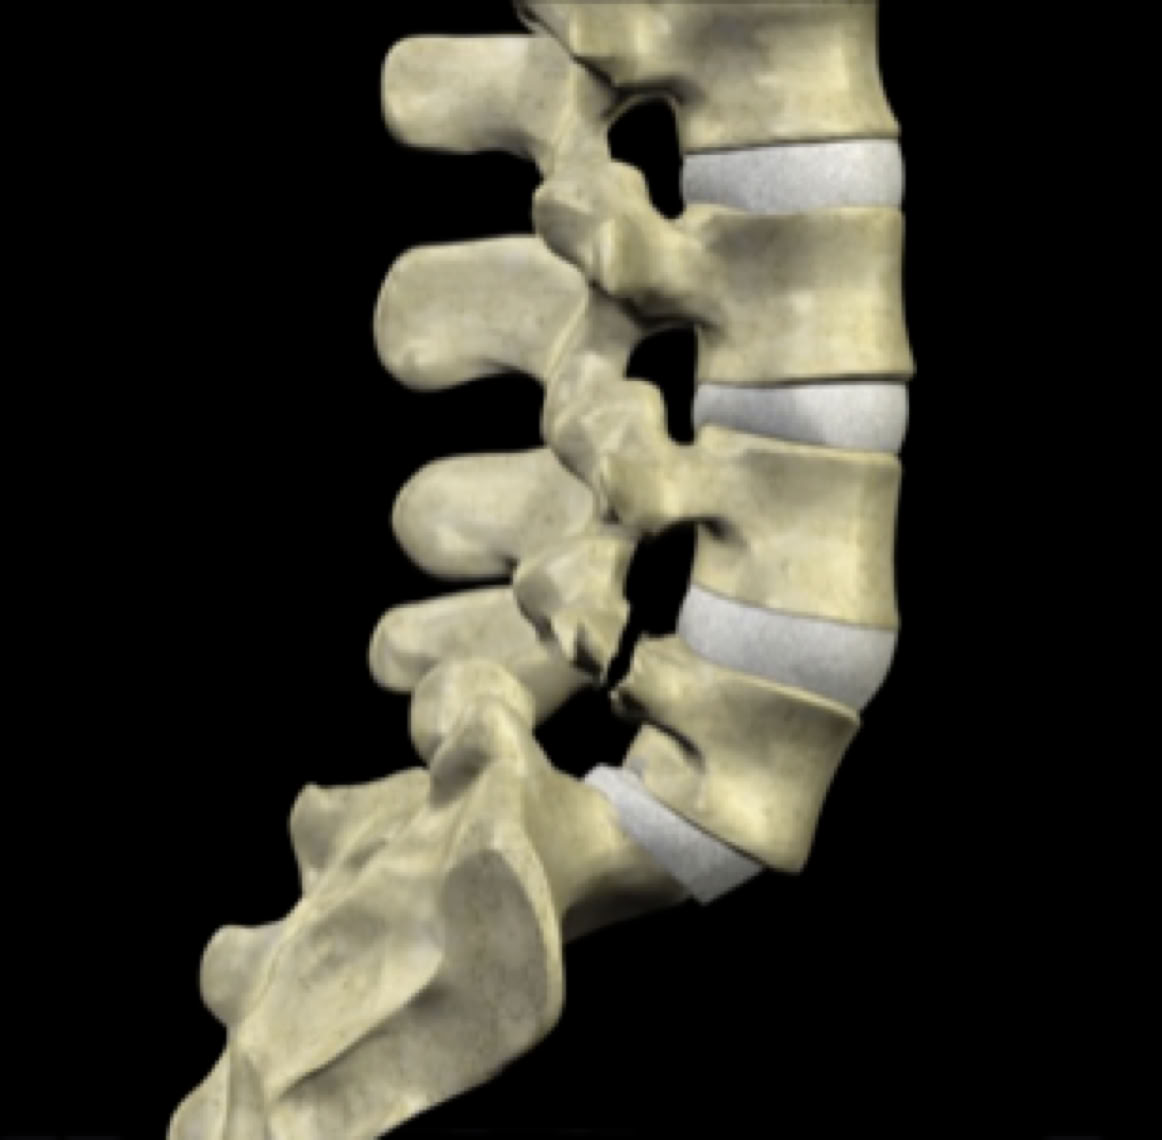

To fully understand how these mechanisms lead to slippage, it’s important to first grasp the anatomy of the vertebral motion segment. Each level of the spine functions as a three-joint complex: two facet joints at the back and a large intervertebral disc in the front. This "tripod" structure provides significant stability, supports the weight above each spinal level, and facilitates movement in all directions. When the disc remains healthy, it can effectively absorb these forces over many years without causing symptoms.

normal motion segment